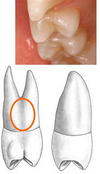

Occlusal view: outline form

More rounded on maxillary 2nd premolar

Maxillary occlusal view: lingual cusp displacement

Greater mesial displacement of lingual cusp on maxillary 1st premolar

Maxillary occlusal view: mesial surface convexity

Greater on maxillary 2nd premolar

Maxillary occlusal view: buccal ridge prominence

More prominent on maxillary 1st premolar

Maxillary occlusal view: mesial marginal ridge groove

Present on maxillary 1st premolar

Maxillary occlusal view: central developmental groove lengths

Slightly longer on maxillary 1st premolar

Maxillary occlusal view: marginal ridge width

Wider on maxillary 2nd premolar

Maxillary occlusal view: location of pits

Maxillary 1st premolar = closer to marginal ridges

Maxillary 2nd premolar = closer to center of tooth

Maxillary occlusal view: mesio-buccal and disto-buccal line angles

More prominent and angular on maxillary 1st premolar